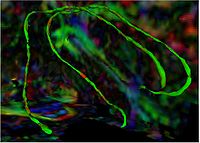

Tubular Surface Segmentation FrameworkWe have proposed a new model for tubular surfaces that transforms the problem of detecting a surface in 3D space, to detecting a curve in 4D space. Besides allowing us to impose a "soft" tubular shape prior, this also leads to computational efficiency over conventional surface segmentation approaches. More... New: V. Mohan, G. Sundaramoorthi, A. Stillman and A. Tannenbaum. Vessel Segmentation with Automatic Centerline Extraction using Tubular Surface Segmentation. September 2009. Proceedings of the Workshop on Cardiac Interventional Imaging and Biophysical Modelling (CI2BM'09), Int Conf Med Image Comput Comput Assist Interv. 2009. New: V. Mohan, G. Sundaramoorthi and A. Tannenbaum. Tubular Surface Segmentation for Extracting Anatomical Structures from Medical Imagery, IEEE Transactions on Medical Imaging, volume 29, 2011, pp. 1945-1958.

Group Study on DW-MRI using the Tubular Surface ModelWe have proposed a new framework for performing group studies on DW-MRI data sets using the Tubular Surface Model of Mohan et al. We successfully apply this framework to discriminating schizophrenic cases from normal controls, as well as towards visualizing the regions of the Cingulum Bundle that are affected by Schizophrenia. More...